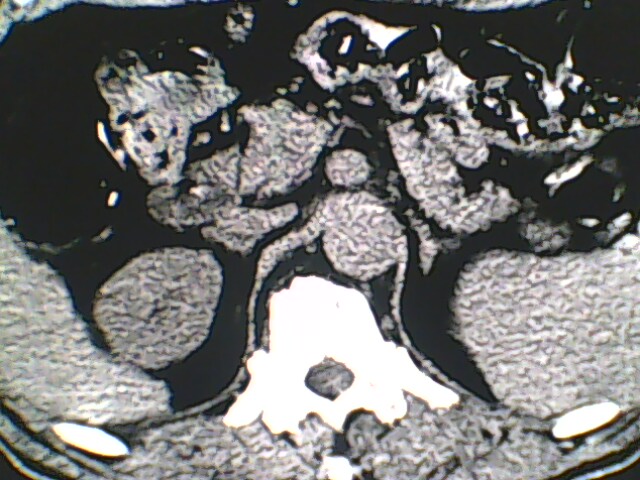

男,56岁,高血压,临床怀疑肾上腺问题,肝脏怎么那么高啊?能描述一下么?

右侧膈膨升,间位结肠,胸腰椎退行性骨关节病,右侧肾上腺可疑增生(图像颗粒太粗,窗太窄,不好看)。

支持 右侧膈膨升,间位结肠;胸腰椎退行性骨关节病;双侧肾上腺可疑增生。